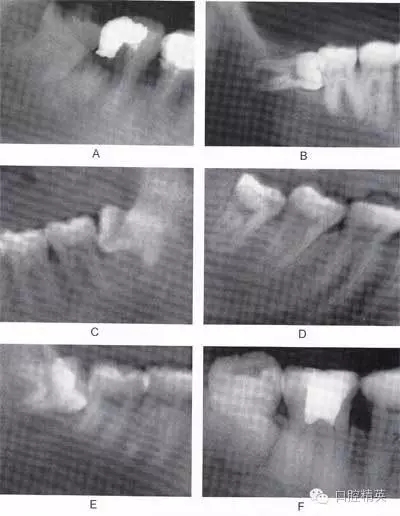

圖6-2 根據(jù)阻生牙相對于下頜升支前緣位置關系分為:第1類 (圖A):下頜升支前緣和第二磨牙遠中面之間有足夠的間隙容 納第三磨牙牙冠;第2類(圖B):約一半的第三磨牙牙冠被下 頜升支前緣覆蓋;第3類(圖C):第三磨牙全部位于下頜升支 前緣內

A

B

C

圖6-3 相對于聆平面的位置關系分為:A分類(圖A):第三磨牙殆面平齊于第二磨牙聆面;B分類(圖B):第三磨牙(牙合)面 位于第二磨牙殆面和牙頸部平面之間;C分類(圖C):第三磨牙(牙合)面低于第二磨牙的牙頸部平面。一般情況下,近中阻生拔除難度比垂直阻生小,垂直阻生比水平阻生小,水平阻生比遠 中阻生小;第1類比第2類簡單,第2類比第3類簡單;A分類比B分類簡單,B分類比C分類簡單。另外拔牙難度與牙齒形態(tài)、 患者年齡、牙周骨質密度以及與下牙槽神經(jīng)管的關系也有關聯(lián)。 骨質密度越大,年齡越大,患牙牙周骨質鈣化程度越高,越難拔除.

圖6-4 以上類型的下頜第三磨牙由于根阻力大,一般需要分根才能拔除

A.多根牙 B。超長根 C。牙根向遠中彎曲 D。兩根環(huán)抱 E。根分叉大 F,根端肥大 G。彎根 H.U型根(X線片及離體牙)

圖6-5 以上類型的下頜第三磨牙由于根阻力小,一般不需分根,即可拔除。

A.合并根 B.短根 C.椎形根 D.牙根向遠中彎曲 E.根分叉小 F.根尖未完全形成